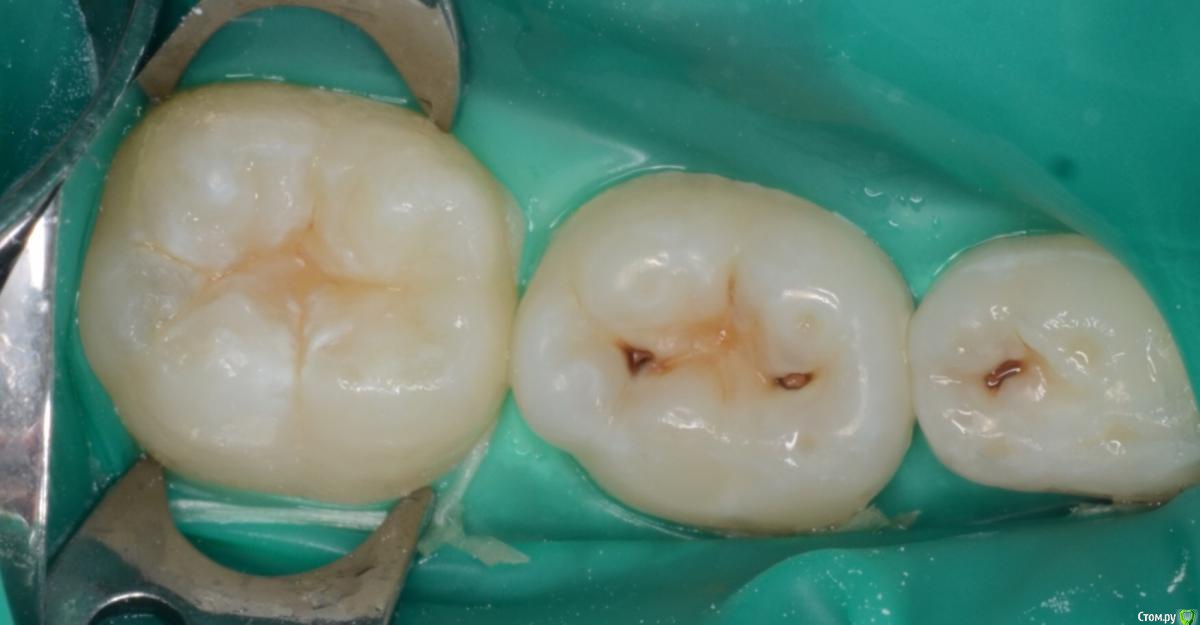

CRAZYDUCK Опубликовано 20 мая, 2018 Автор Поделиться Опубликовано 20 мая, 2018 Вовремя замеченный кариес не успеет превратиться в пульпит . Поверхностный кариес контактных поверхностей 6.5 и 6.4 зубов, подтверждённый RVG исследованием . Серёже 3,5 года , но он большой молодец , продолжительность 45 минут ( анестезия, коффердам , преп турбиной и рондофлекс , пломбирование и полировка. 1 Ссылка на комментарий